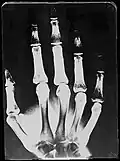

X-Ray image of right hand with no details in the bones at the bottom of the image -

Original: X-Ray image of right Hand;

1st. order equidensities after pseudo-solarization of original -